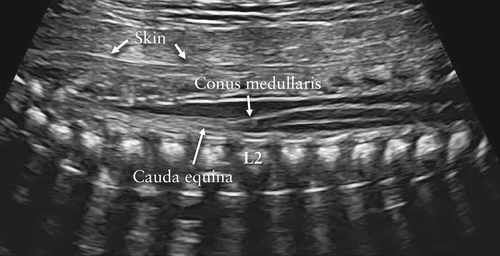

胎儿脊柱的详细检查需要专业知识和细致的扫描,其结果在很大程度上取决于胎儿的位置。因此,在每个平面上对胎儿的脊柱进行全面而详细的评估并不是筛查的一部分。最常见的严重脊柱异常之一是开放性脊柱裂,通常与颅内解剖结构异常有关:高达97%的病例出现所谓的“香蕉征”,这是由Chiari-II畸形引起的,但是,如果技术上可行,则应寻求胎儿脊柱的纵切面,因为它可能至少在某些情况下揭示出其他脊柱畸形,包括椎骨异常和骶骨发育不全,尽管即使对专家而言,后者的诊断也可能具有挑战性, 因为妊娠中期尾椎的生理性非骨化状态。在正常情况下,孕18-24周的脊柱矢状切面显示出围绕神经管的三个椎骨骨化中心(一个是椎体,另外是每一侧在椎板与椎弓根交界处)。根据超声波束的方向,它们显示为两条或三条平行线(图3)。在单个椎骨的横断面上,三个骨化核的显示最佳(图4)。另外,应该尝试以横切或纵切的来证明覆盖脊柱的皮肤的完整性。

图3下胸部胎儿脊柱纵切面。以未骨化的棘突为声学窗口,演示了神经管的内容。清楚地显示了髓质圆锥,并且在妊娠中期通常位于L2的水平。它的尖端应指向椎体的前面,并向后充填神经管。请注意,沿胎儿背部观察到的完整皮肤为高回声线。